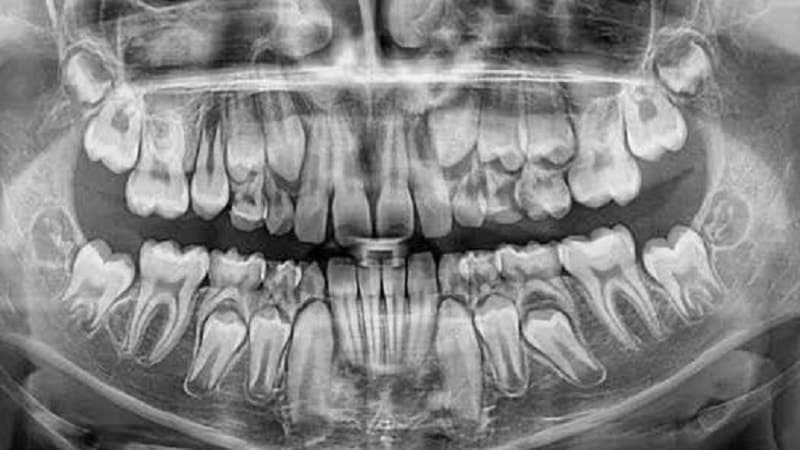

Необходимость проведения рентгенографии

Если у родителей возникают сложности в определении, является ли зуб молочным или коренным, можно воспользоваться рентгеновским снимком. Этот метод позволяет быстрее установить тип зуба в ротовой полости.

Когда размеры или форма корней значительно отличаются, это может свидетельствовать о наличии постоянного зачатка в корне. Физиологическая замена зуба может происходить с задержкой, поэтому важно знать, как выявить причины этой задержки и оценить состояние корней.

Если постоянного зачатка нет, необходимо сохранить молочный зуб и следить за состоянием его корня. В случае быстрого рассасывания рекомендуется подготовиться к протезированию.

Если на рентгеновском снимке виден коренной зуб, а молочный не выпадает, стоит обратиться к ортодонту для консультации.

Специалист на основе снимка сможет определить толщину кости и угол наклона по отношению к соседним зубам. При правильном расположении коренного зуба и удалении молочного можно ожидать его самостоятельного прорезывания.